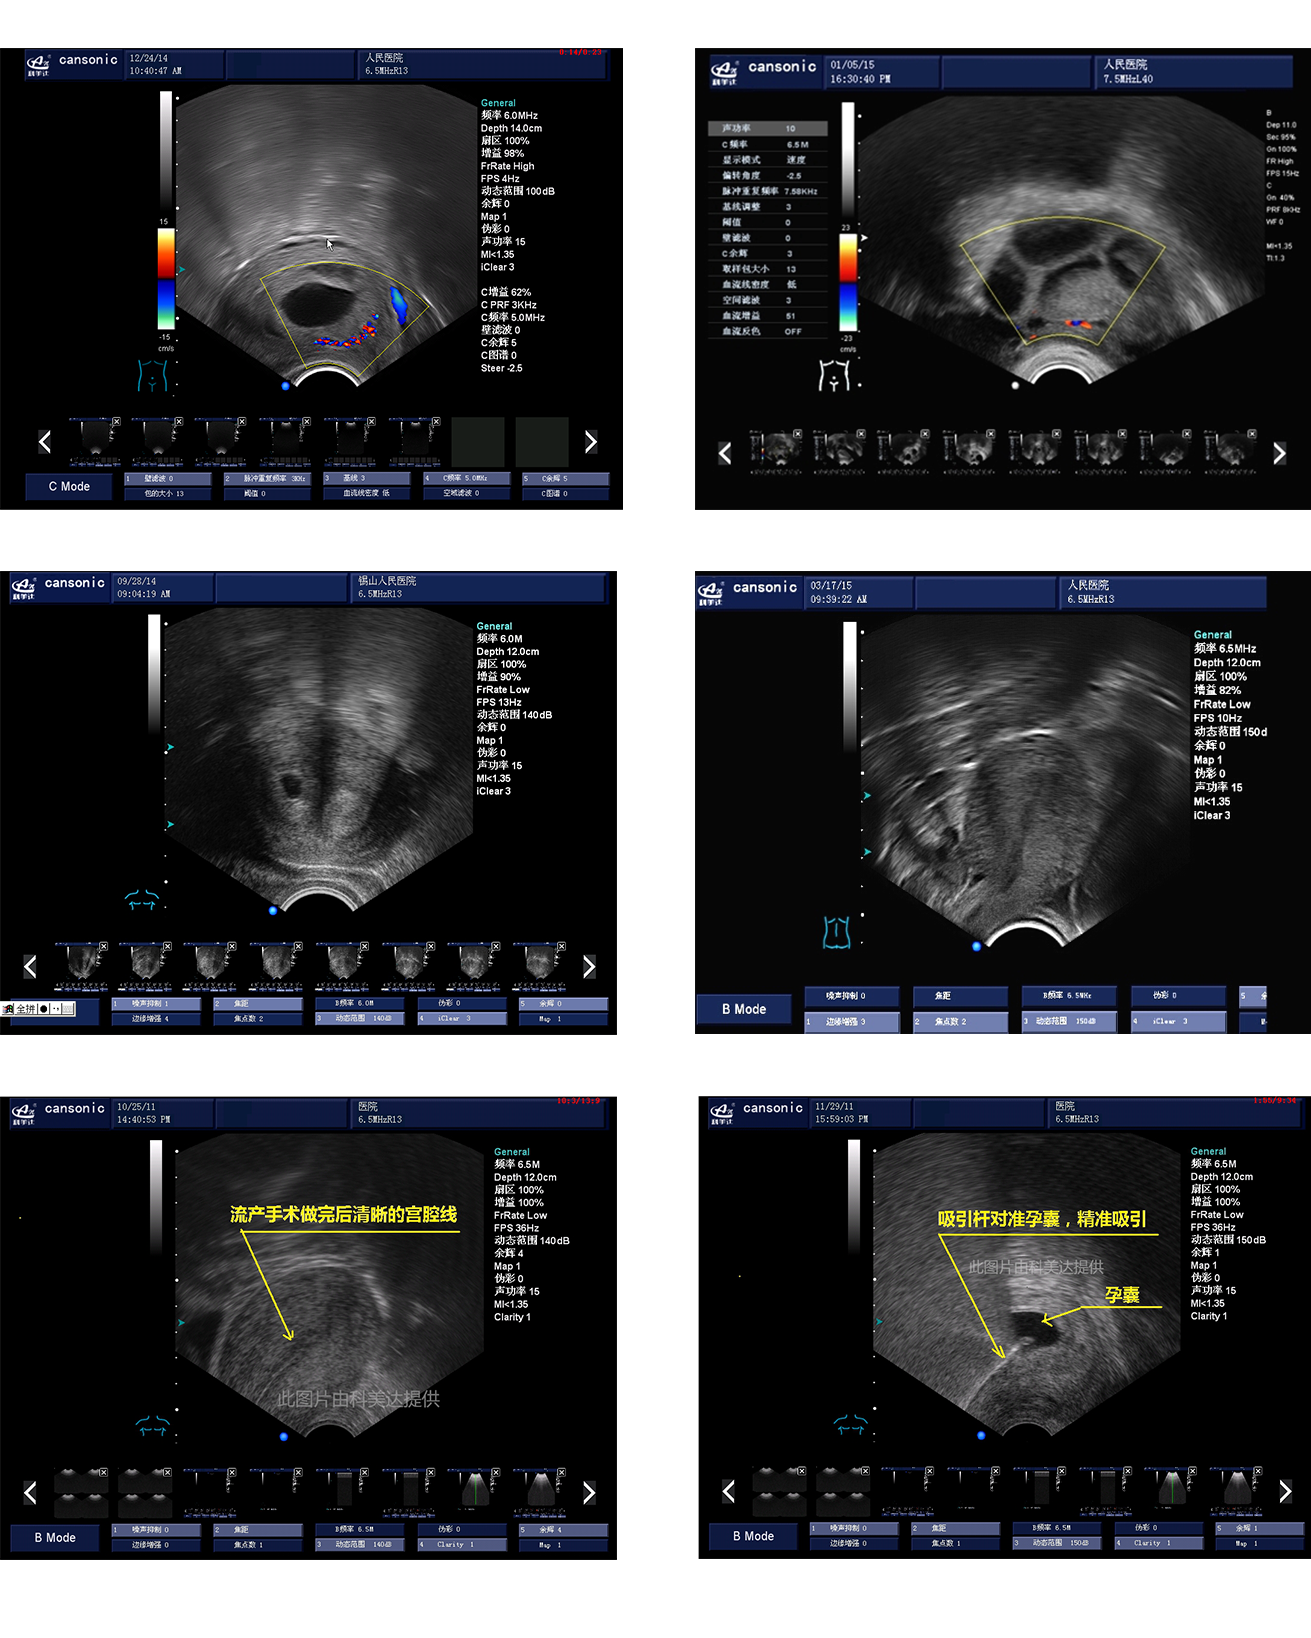

臨床圖示

1、融合業(yè)內(nèi)高端的硬件工藝及智能后處理算法,結(jié)合規(guī)范的操作流程,實(shí)現(xiàn)對(duì)宮腔手術(shù)的全程監(jiān)測(cè)

2、精準(zhǔn)數(shù)字濾波技術(shù),有效降低多普勒噪聲及運(yùn)動(dòng)偽像,提升血流及多普勒超聲圖像

4、能量多普勒POWER成像模式彩色多普勒Color成像模式

5、血流靈敏度高,清晰可見